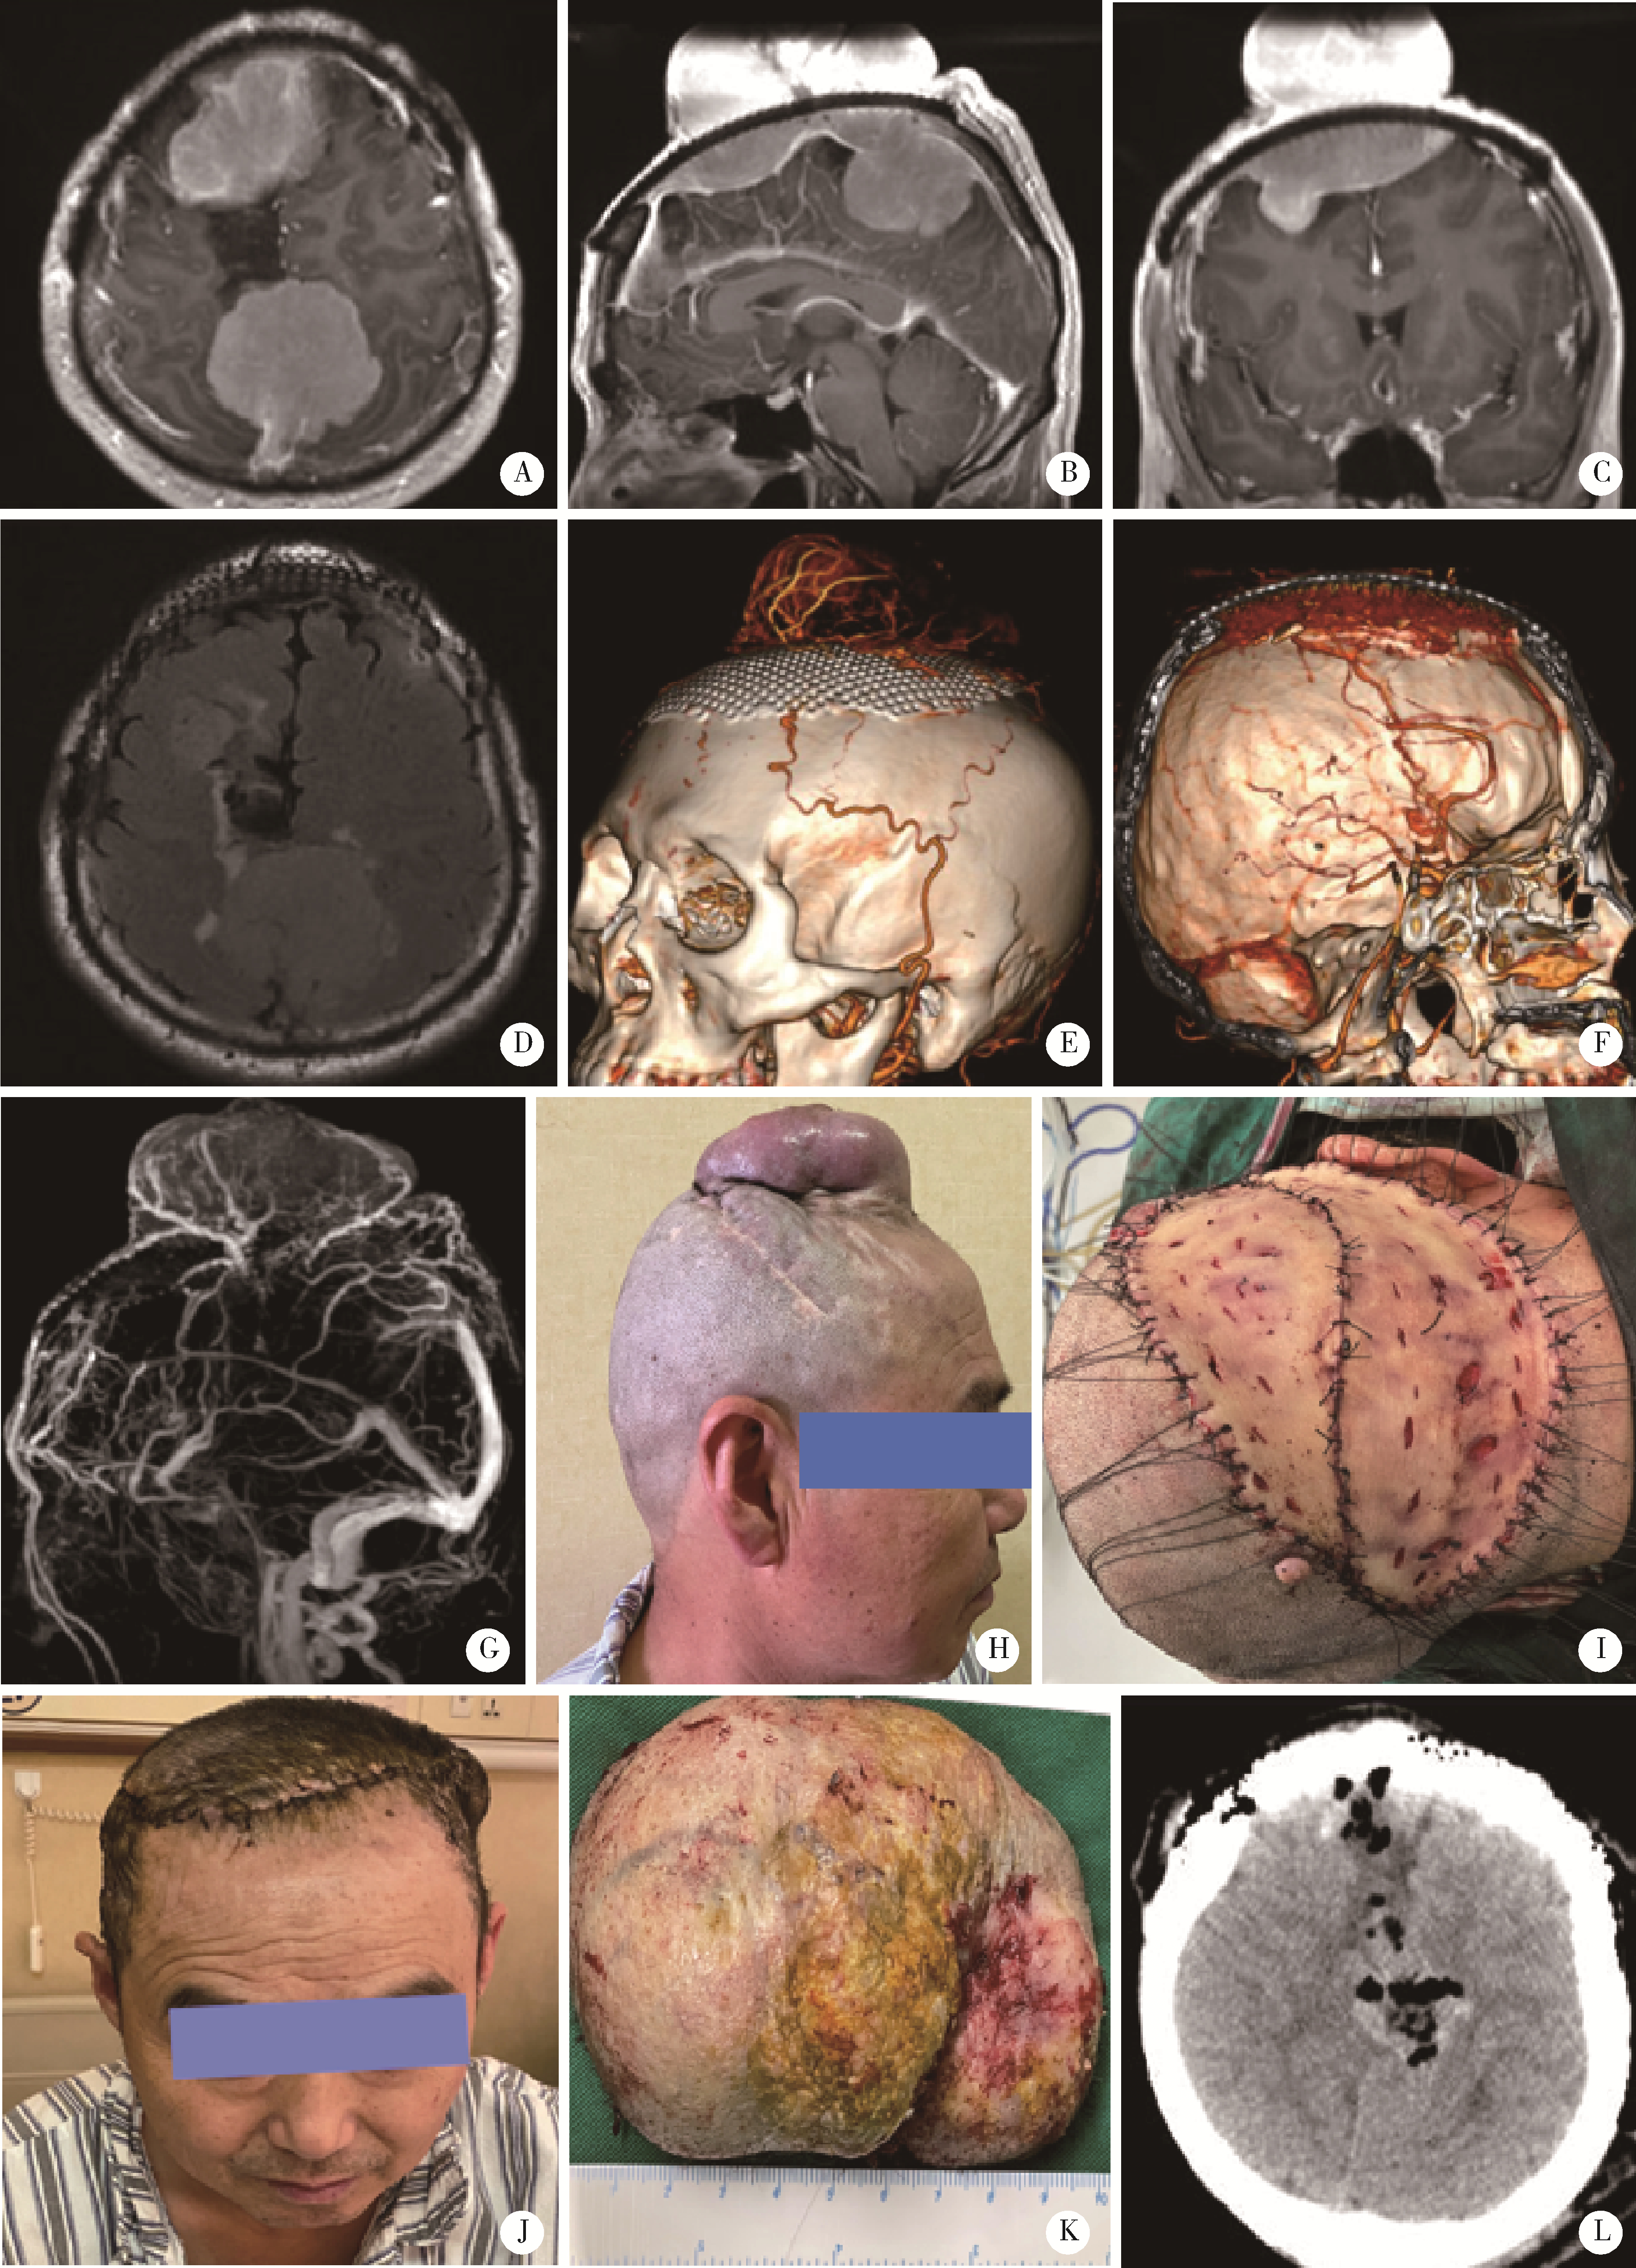

图2

男,53岁,既往额顶部3次脑膜瘤手术后再次复发"